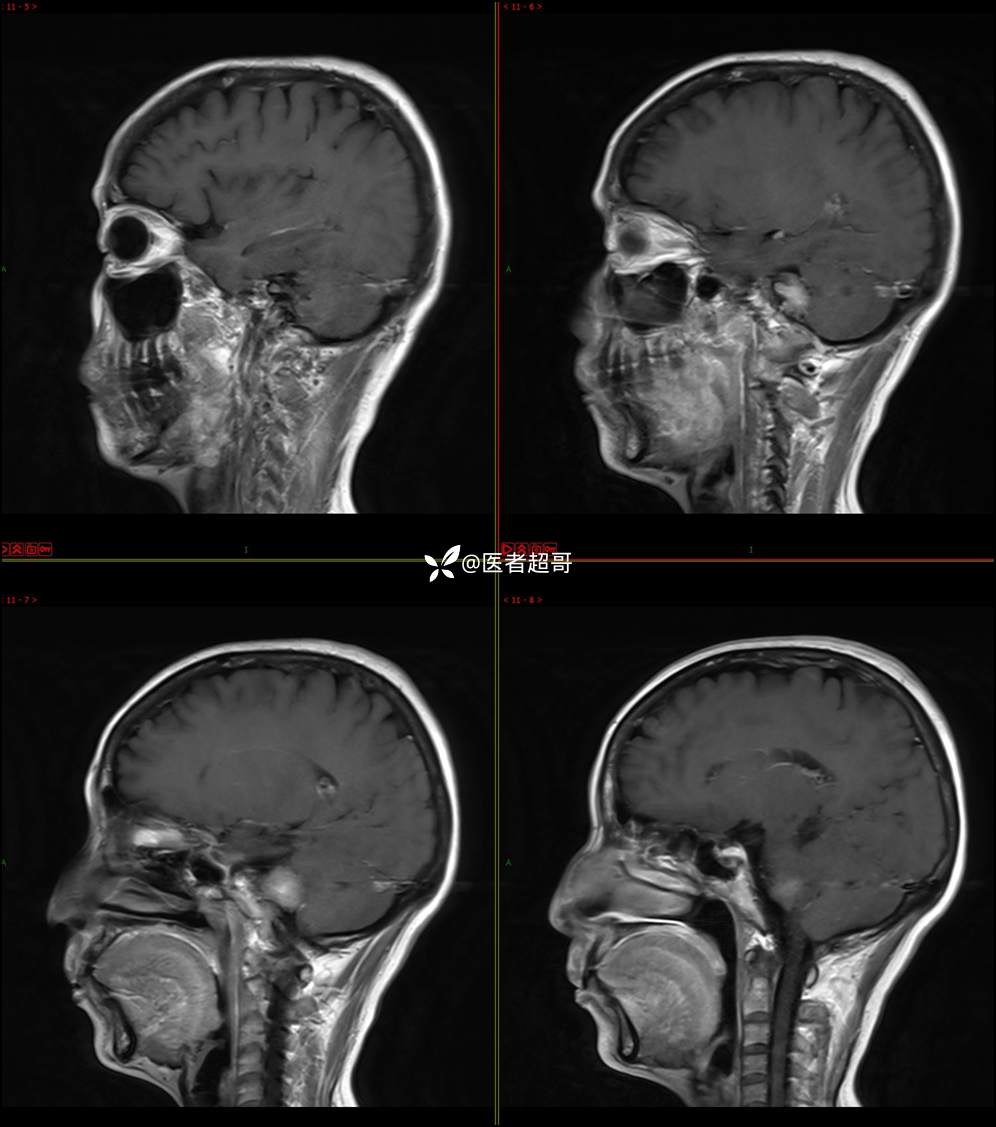

CPA区占位,是鞘瘤?脑膜瘤?请赏析!

主 诉:耳鸣3年,头晕伴恶心4天。

现病史:患者3年前出现耳鸣,蝉鸣音,反复发作,夜间自觉明显,于2018年8月至我院耳鼻喉科就诊,行颅脑CT检查未发现明显异常改变,给予对症处理(具体不详);4天前突发头晕,伴明显恶心,至市人民医院就诊,行颅脑CT未见明显异常,颅脑MRI发现右侧桥脑小脑角区占位性病变。本次发病来无明显头痛,无肢体抽动,无大小便失禁。为求进一步诊治,遂来我院门诊,以“听神经良性肿瘤”收住入院。发病来,患者神志清,精神可,二便正常,饮食可,睡眠不佳,近期体重无明显变化,否认癫痫发作病史。